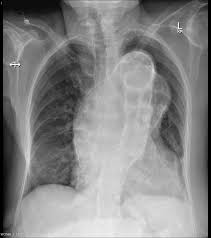

Chest X Ray To Check Fitness Is Outdated Health Gulf News

Chest X Ray To Check Fitness Is Outdated Health Gulf News from gulfnews.com